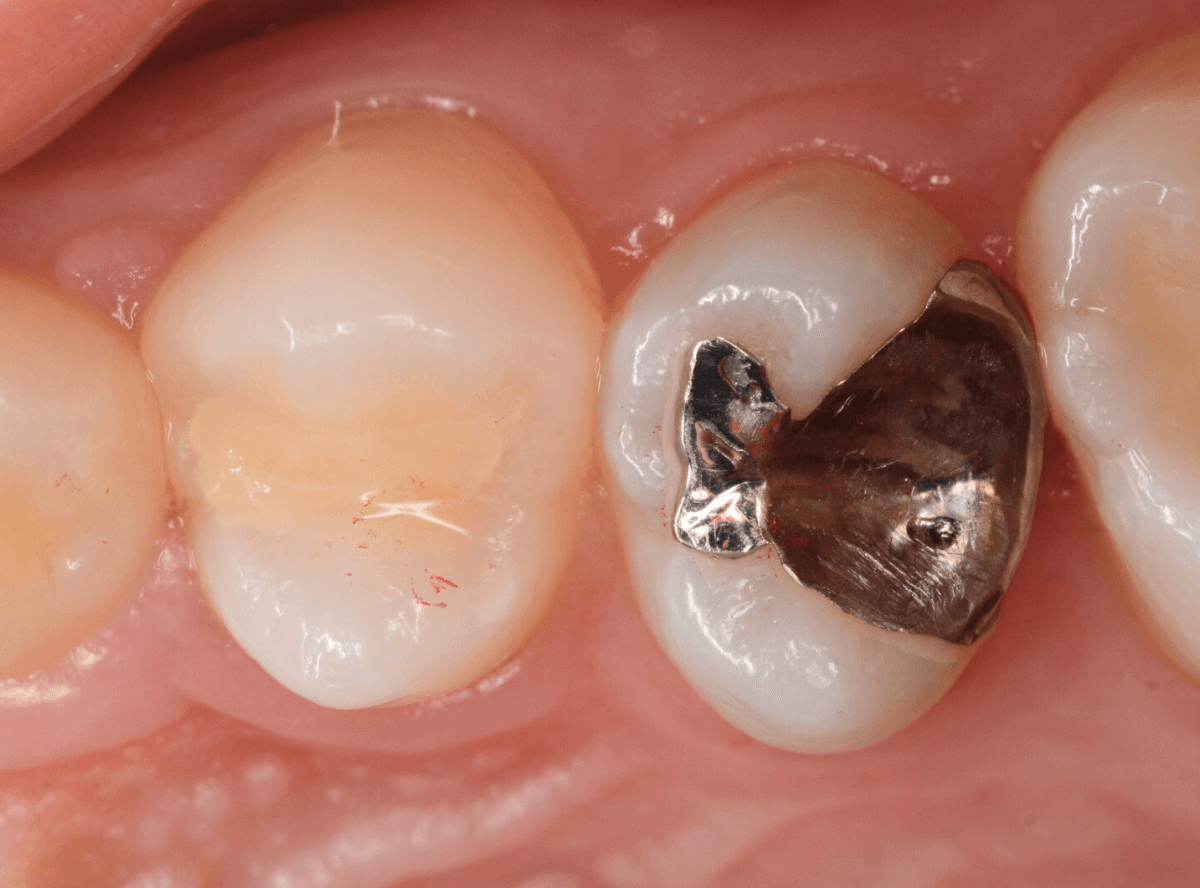

検診で、金属のつめ物のの中と、歯の側面に虫歯が見つかった方です。

まずは、手前(左)側の治療です。

こちらが、お口の中を見たところです。

〇部の中に虫歯があると思われます。

今回のように、金属のつめ物やレジン治療をしてある歯の側面の虫歯の診断はわかりづらく、難しいです。

金属のつめ物を外したところです。

この白いセメントの中に虫歯があると思われます。